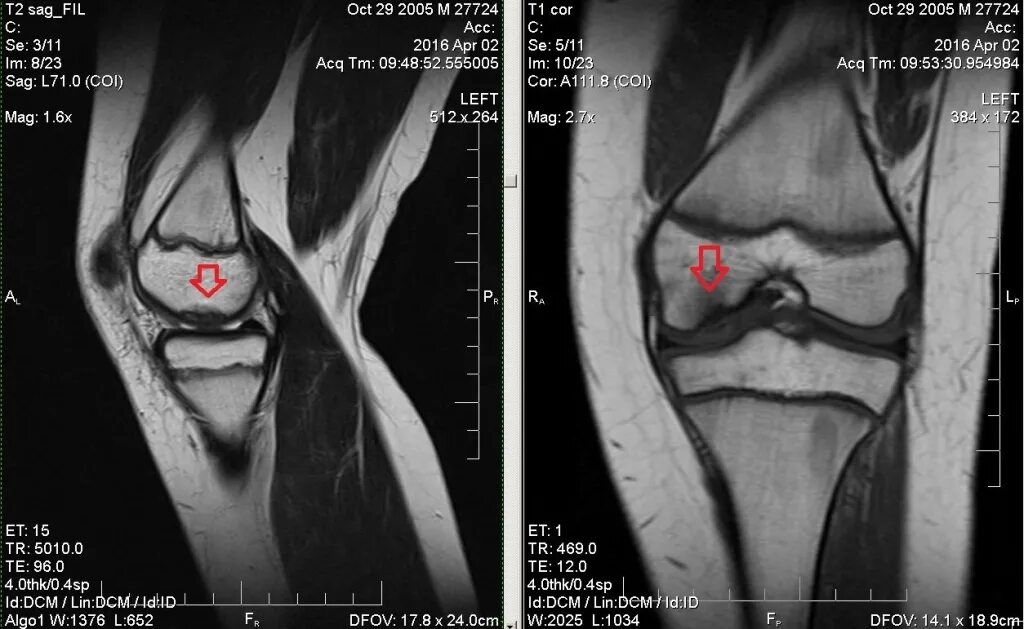

Что показывает мрт коленного сустава у взрослых